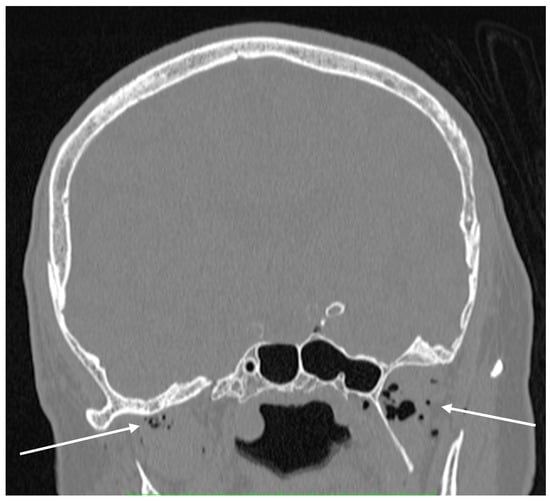

Figure 5. Coronal plane of the head’s CT scan. Gas bubbles are detected in the lumen of blood vessels of the face and intracranially (arrows).

Due to the high solubility of carbon dioxide, the diagnostic imaging performed in a short interval after the SCA exceptionally illustrates the mechanism of gas bubble transmission into the vasculature of both vena cavae. We were able to visualize the presence of CO2 gas in the CT scan of the head in Figure 5 and in the distal section of the CT scan of the abdomen and pelvis which includes a section of the lower extremities in Figure 3. The explanation for such extensive gas transfer and its presence in the internal jugular vein, craniofacial tissues, sigmoid sinuses of the superior vena cava (Figure 5) and in the lumen of the femoral veins (Figure 3) may be explained by the CPR performed, and the possibility of very high pressures of the gas used, which may have been facilitated by the hypovolemic position and status of the patient.